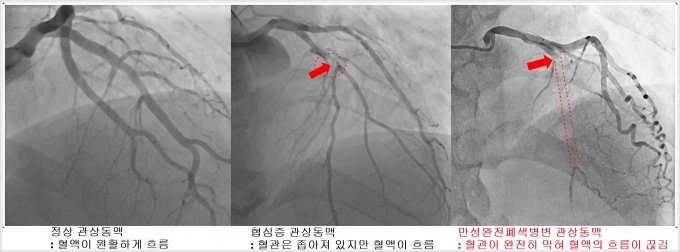

[µ¥Àϸ®¸Þµð ±è¹Î¼ö ±âÀÚ] ½ÉÀåÇ÷°üÀÌ 100% ¸·Çû´õ¶óµµ ±× ÁÖÀ§·Î ´Ù¸¥ Ç÷°üµéÀÌ Àß ¹ß´ÞµÅ ½ÉÀå¿¡ Ç÷¾×À» °ø±ÞÇϰí ÀÖ´Ù¸é °íÀ§Çè, °íºñ¿ëÀÎ ½ºÅÙÆ® ´ë½Å ¾à¹°·Îµµ È¿°úÀûÀÎ Ä¡·á°¡ °¡´ÉÇÏ´Ù´Â ¿¬±¸°á°ú°¡ ³ª¿Í °ü½ÉÀ» ²ö´Ù.

½ÉÀåÇ÷°üÀÌ ¿À·£ ½Ã°£¿¡ °ÉÃÄ µ¿¸Æ°æÈ­°¡ ¼­¼­È÷ ÁøÇàµÇ¸é¼­ °á±¹¿£ ¿ÏÀüÈ÷ ¸·Çô ¹ö¸®¸é ‘¸¸¼º¿ÏÀüÆó»öº´º¯(CTO)’ÀÌ µÈ´Ù. Áö±Ý±îÁö ½ºÅÙÆ®¸¦ »ðÀÔÇÒ °ÍÀÎÁö, ¾Æ´Ï¸é ¾à¹°·Î¸¸ Ä¡·áÇÒ °ÍÀÎÁö¿¡ ´ëÇÑ ³í¶õÀÌ Àü¼¼°è ½ÉÀåÇаèÀÇ Å« À̽´¿´´Ù.

ÀÌ´Â ¸¸¼º¿ÏÀüÆó»öº´º¯À¸·Î Ç÷°üÀÌ ¸·È÷´õ¶óµµ ¿À·£ ¼¼¿ùµ¿¾È ÁÖº¯¿¡ »õ·Î¿î ¿ìȸ·Î¸¦ ¸¸µé¾î ½ÉÀå¿¡ Ç÷·ù¸¦ °ø±ÞÇÏ°í ½ÉÀå±â´É ¶ÇÇÑ Á¤»óÀÎ °æ¿ì¿¡´Â ¾à¹°Ä¡·á·Îµµ È¿°úÀûÀ¸·Î Ä¡·áÇÒ ¼ö ÀÖ´Ù´Â °ÍÀ» ÀǹÌÇÑ´Ù.

¸¸¼º¿ÏÀüÆó»öº´º¯Àº ½Ã°£ÀÌ Áö³ª¸é¼­ Çù½ÉÁõ Áõ¼¼°¡ ¾ÇÈ­µÇ°í ½ÉºÎÀüÀ¸·Î ÁøÇàµÉ ¼ö ÀÖ´Ù. ´ëºÎºÐ ȯÀÚ´Â ÁÖÀ§ ´Ù¸¥ Ç÷°ü¿¡¼­ Ç÷·ù °ø±ÞÀ» ¹Þ±â ¶§¹®¿¡ ½ÉÀå±â´ÉÀÌ Á¤»óÀ̰í Áõ»óµµ °ÅÀÇ ¾ø°Å³ª °æ¹ÌÇÏ´Ù.

°ü»óµ¿¸ÆÀÇ ÀϺΰ¡ ¸·È÷´Â Çù½ÉÁõÀ̳ª ½ÉÀåÇ÷°ü ¾ÈÀÇ Á×»ó¹ÝÀÌ ÅÍÁö¸é¼­ °©Àڱ⠸·Çô ½ÉÀå±ÙÀ°ÀÇ ±«»ç¸¦ ÀÏÀ¸Å°´Â ½É±Ù°æ»öÁõ¿¡¼­´Â ¸·Èù Ç÷°üÀ» ¶Õ´Â ½ºÅÙÆ® ½Ã¼úÀÌ ±âº» Ä¡·á¹ýÀ¸·Î ÀÚ¸®¸Å±èÇϰí ÀÖ´Ù.

°ü»óµ¿¸Æ ¸¸¼º¿ÏÀüÆó»öº´º¯¿¡¼­µµ ½ºÅÙÆ® Ä¡·á¹ýÀº ±â±¸³ª Àç·áÀÇ ¹ßÀü°ú ½Ã¼ú ÀÇ»çµéÀÇ ¼÷·Ãµµ°¡ ³ô¾ÆÁö¸é¼­ ¼º°ø·ü°ú ÇÕº´Áõ ¸ðµÎ ÁÁ¾ÆÁö°í ÀÖÁö¸¸, ¾ÆÁ÷ ´Ü¼ø Çù½ÉÁõ¿¡ ºñÇØ ½Ã¼ú ³­À̵µ°¡ ³ô°í ÇÕº´Áõ ¹ß»ýÀÇ À§Çè°ú ºñ¿ëµµ ³ô´Ù.